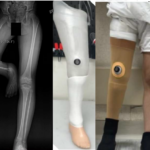

Islamabad — A comprehensive five-day KAFO training program successfully concluded at Rehab Initiative Islamabad, organized in collaboration with ICRC Pakistan. The training brought together professionals from across the prosthetics and